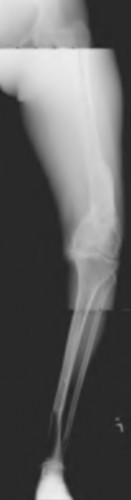

A 67 year-old woman sustained an ACL tear while playing basketball when she was 35 years-old. She has noted progressive leg deformity and episodes of giving way, and now has pain preventing activity. Non-operative management has failed to provide relief. Treatment should consist of?

The radiograph seen in Figure A reveals varus alignment of the knee, with medial tibial deficiency; from this X-ray the patient appears to have unicompartmental arthritis. Treatment options for unicompartmental arthritis include high tibial osteotomy, interpositional arthroplasty, unicondylar knee replacement and total knee replacement. Interpositional arthroplasty became popular in the 1950’s when early outcomes analysis seemed to indicate good results; long term follow up in one study found 0/12 excellent results, with all patients requiring conversion to TKA. This procedure is no longer recommended due to the poor long term outcomes.

While an osteotomy is still used for young and active patients, unicompartmental or total knee arthroplasty have largely replaced this treatment in older patients. Advantages of UKA and TKA include more predictable relief of pain, quicker recovery, and better long-term results. Criteria for UKA include limited unicompartmental disease, no more than a fixed 10 degrees of varus or 5 degrees of valgus deformity from neutral and an intact anterior cruciate ligament with no signs of medial lateral subluxation of the femur on the tibia; this patient is therefore not a good candidate for this procedure.

Total knee arthroplasty can be used to provide predictable pain relief in a patient with unicompartmental and tricompartmental degenerative disease and varus malformation of the knee and for this patient is the best option.